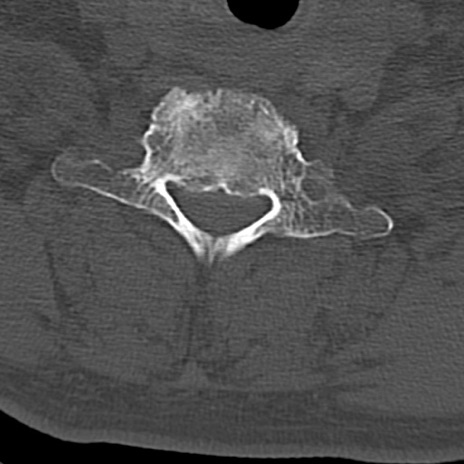

頚椎CT

横断像